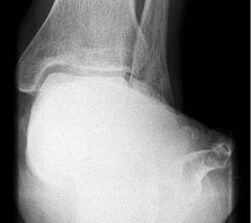

Abbildung Nr. 2: Saltzmannaufnahme zur Bestimmung des Fersenvalgus.

Es konnte, bei präoperativer Unfähigkeit zum einbeinigen Zehenspitzenstand, beim letzten Follow up in 62% der Fälle ein schmerzloser einbeiniger Zehenspitzenstand erreicht werden. Der Saltzmann-Winkel konnte von präoperativ 11° (7-17°) auf 3° (1-8°) korrigiert werden. Der seitliche Metatarsale I Winkel wurde von 18° präoperativ (13-23°) auf 7° (5-13°) postoperativ korrigiert. Der talonaviculare Überdeckungswinkel konnte von präoperativ 10° (4-18°) auf postoperativ 7° (2-15°) reduziert werden.